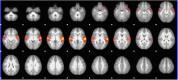

Expanding behavioral and neurobiological evidence affirms benefits of shared (especially parent-child) reading on cognitive development during early childhood. However, the majority of this evidence involves factors under caregiver control, the influence of those intrinsic to the child, such as interest or engagement in reading, largely indirect or unclear. The cerebellum is increasingly recognized as playing a "smoothing" role in higher-level cognitive processing and learning, via feedback loops with language, limbic and association cortices. We utilized functional MRI to explore the relationship between child engagement during a mother-child reading observation and neural activation and connectivity during a story listening task, in a sample of 4-year old girls. Children exhibiting greater interest and engagement in the narrative showed increased activation in right-sided cerebellar association areas during the task, and greater functional connectivity between this activation cluster and language and executive function areas. Our findings suggest a potential cerebellar "boost" mechanism responsive to child engagement level that may contribute to emergent literacy development during early childhood, and synergy between caregiver and child factors during story sharing.